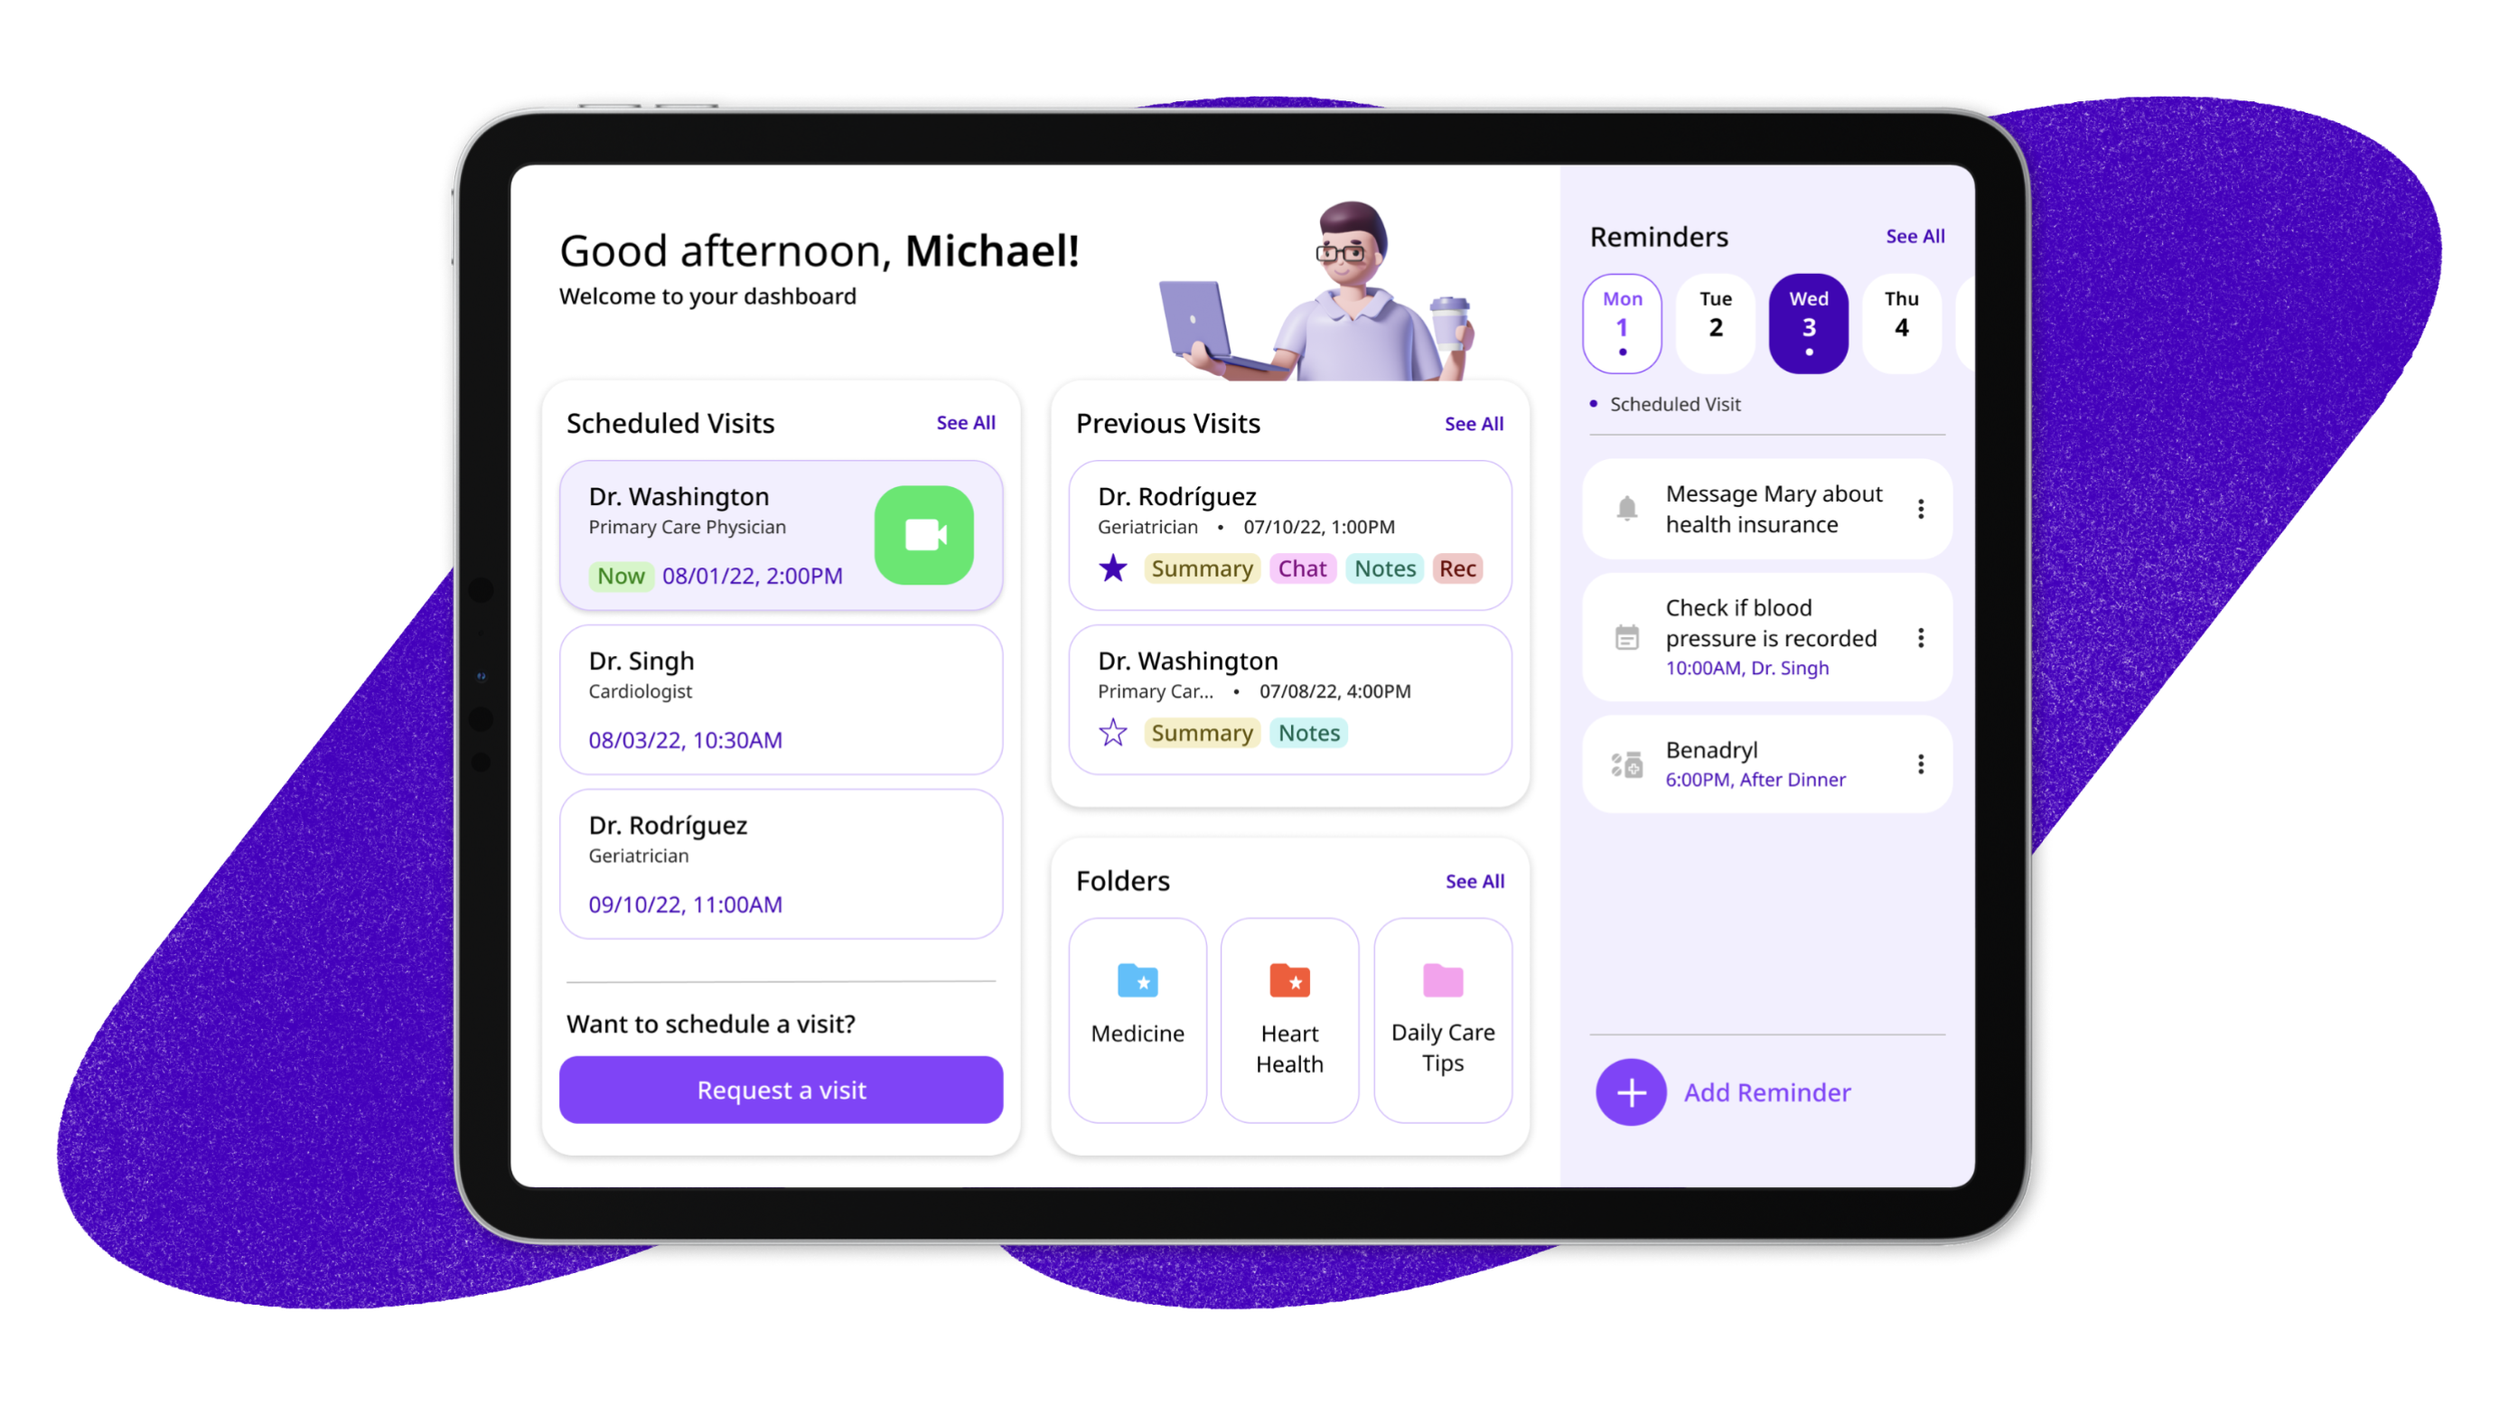

Product and Visual Designer with a drive to turn narratives and complex problems into beautiful, user-friendly solutions.

I’m a designer who enjoys experimenting around and creating narratives through visuals.